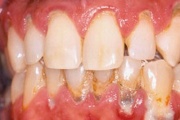

Krooniline parodontiit

Krooniline parodontiit on mikroobide poolt põhjustatud hammaste tugikudede põletik, mille tulemusena tekib progresseeruv alveolaarluu (nähtav röntgenograamil) ja periodontaalligamendi destruktsioon, igemetaskute moodustumine, igeme retsessioon või mõlemad kahjustused kombineeritult. Loe edasi »

- puudulik suuhügieen (5)

- igemepealne hambakivi (5)

- igemealune hambakivi (4)